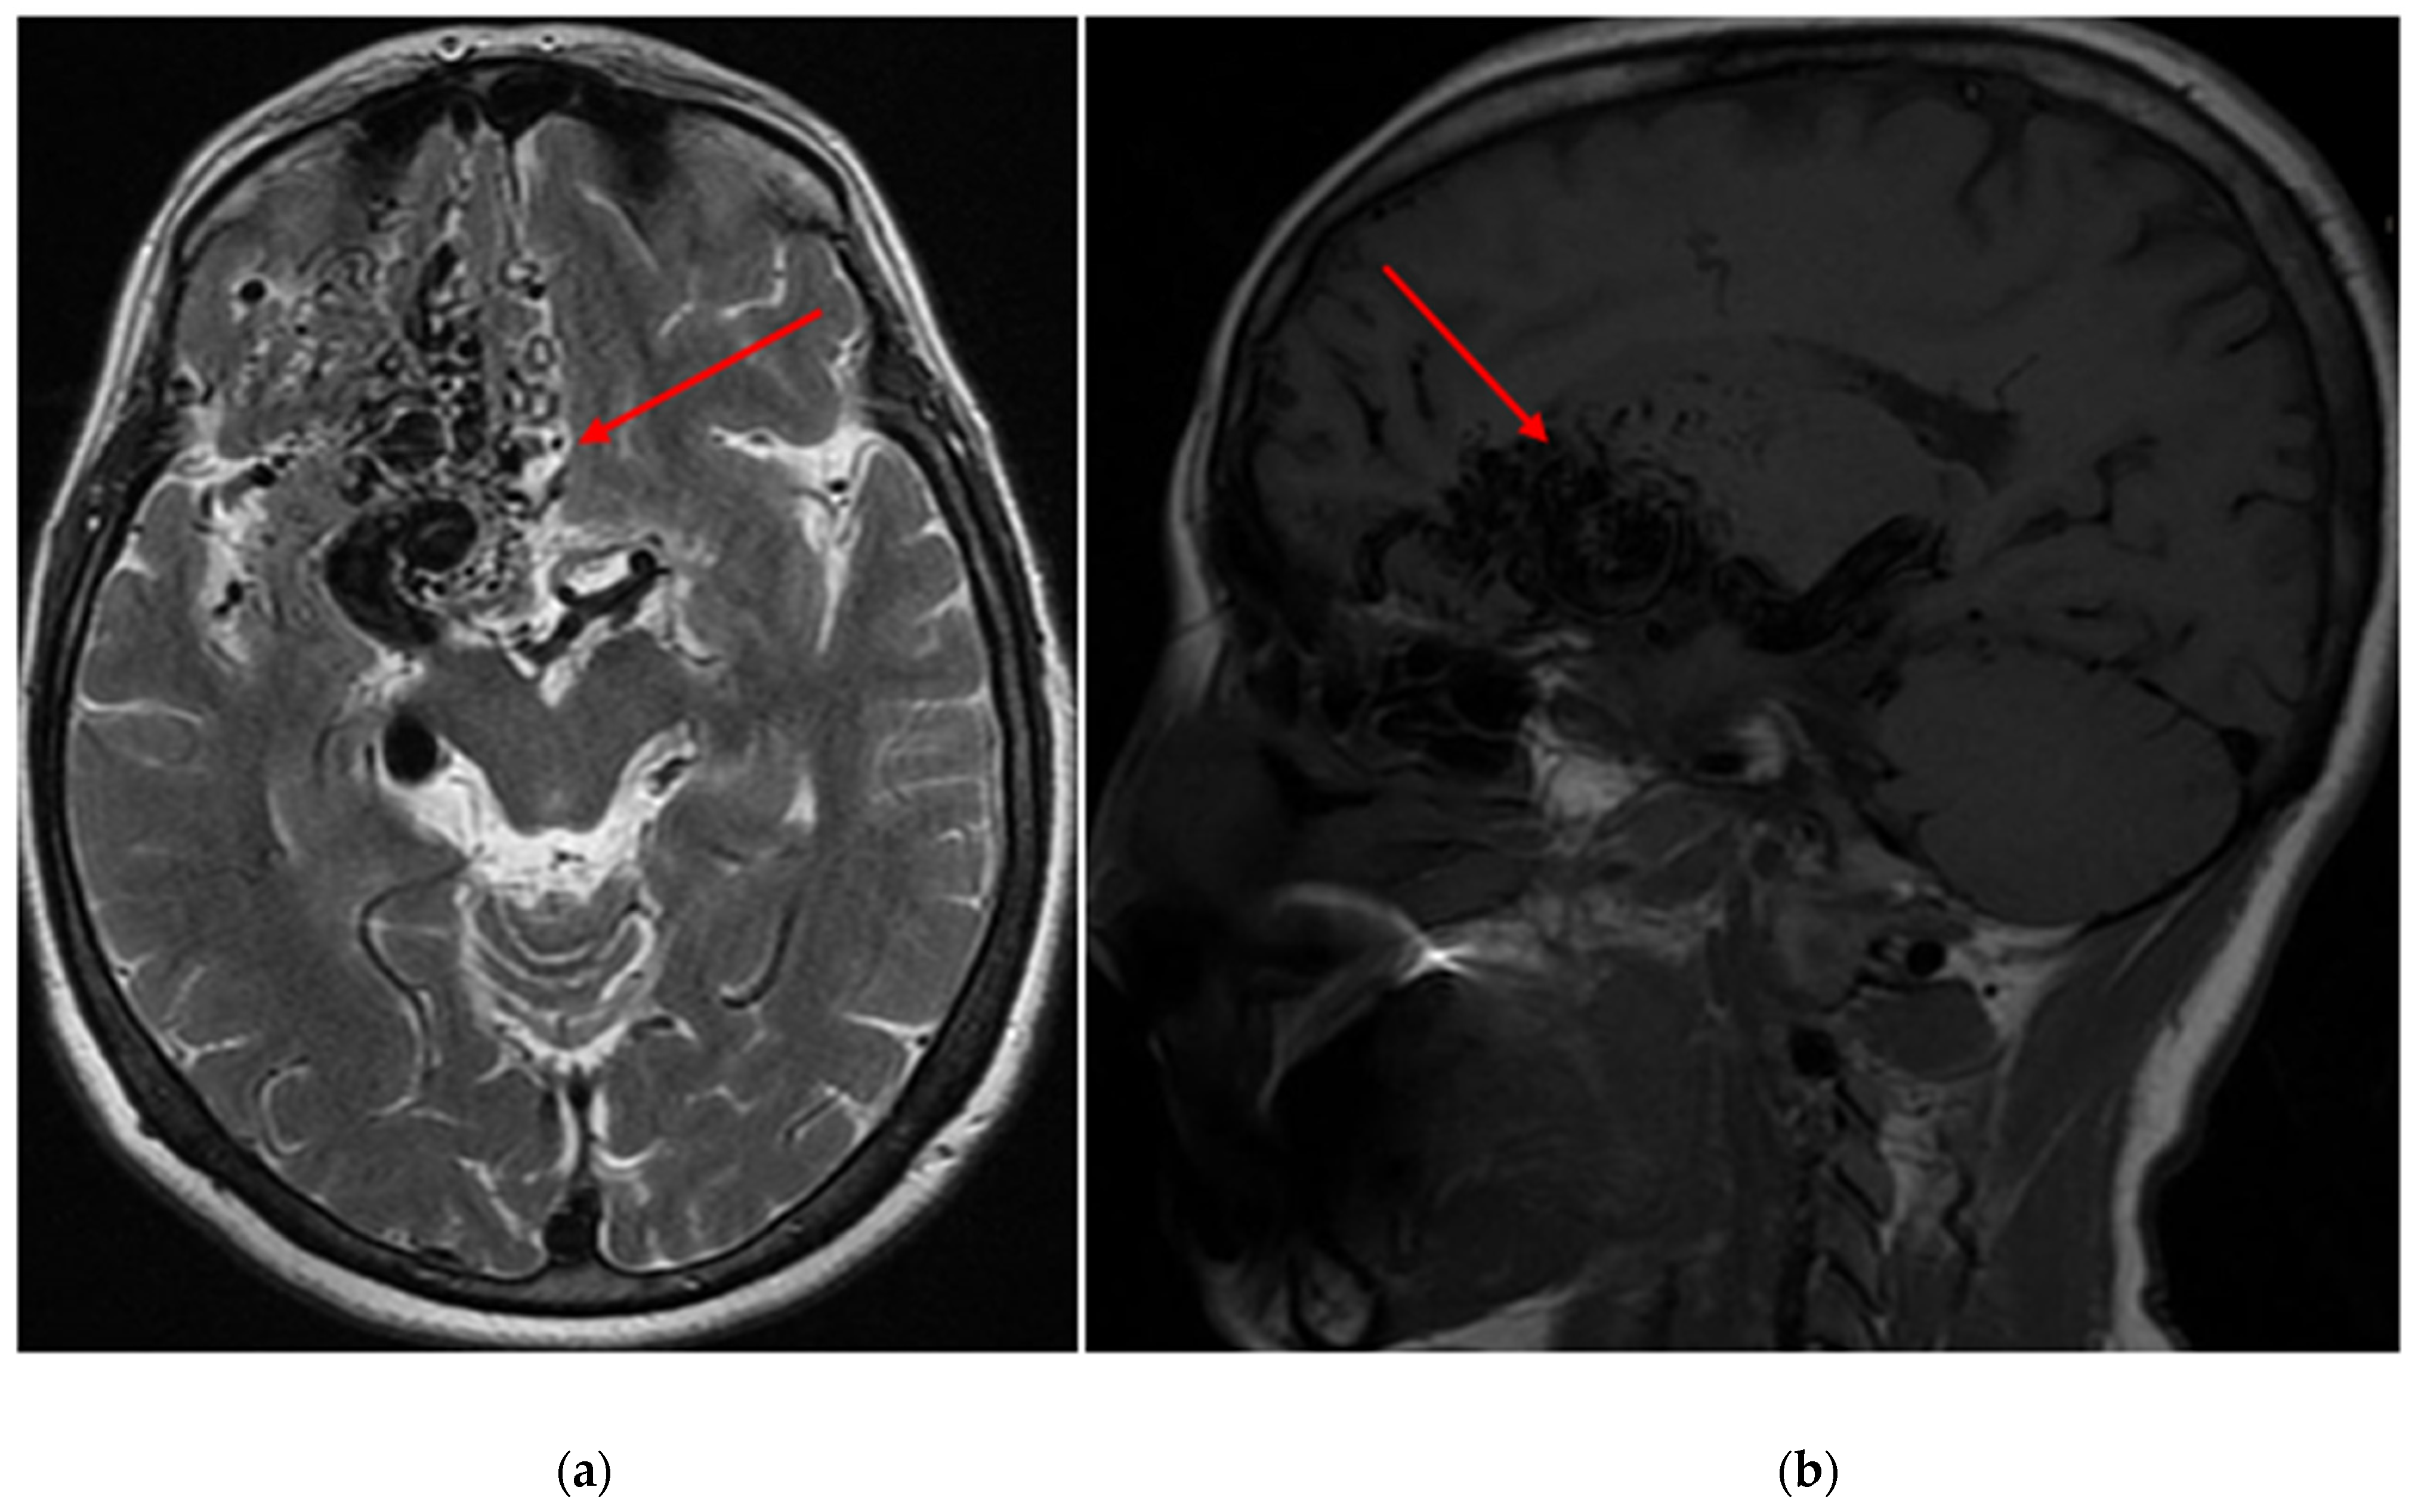

Demographic and clinical data of AVM sampling are shown in Table 1. Seventy patients presented with AVM-associated seizures, and 93 participants had no signs of seizures. Figure 1 and Figure 2 show magnetic resonance imaging (MRI) and cerebral angiography images of the brain of a patient with seizures associated with arteriovenous malformations. In total, 55.71% of subjects with seizures and 56.99% of AVMs without seizures were female. The age and BMI composition of cases and controls were comparable and not statistically significantly different (p > 0.05). Almost 95% of all participants underwent partial or total embolization (Table 2). The most common symptom was rupture, present in 41.98% of all participants.

Figure 1.

(a) An axial T2 magnetic resonance image of the brain depicts an arteriovenous malformation (AVM) situated within the right frontal lobe (red arrows), with a Spetzler-Martin grade of IV assigned to it (b) A sagittal T1 magnetic resonance image of the brain reveals the same AVM located within the right frontal lobe, also assigned a Spetzler-Martin grade of IV.